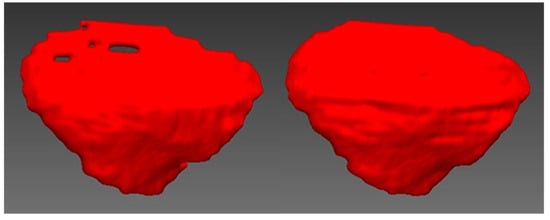

2.1. Design of Cranial Implants Using 3-Matic Software

2.2. Design of Cranial Implants Using MITK Software